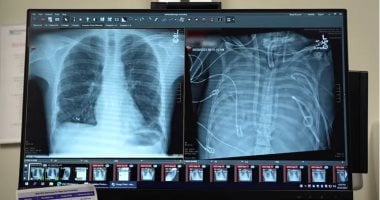

تمكن جراحون في مستشفى نورث وسترن ميديسن في شيكاغو، من إبقاء مريض في حالة حرجة على قيد الحياة لمدة 48 ساعة بعد إزالة كلتا رئتيه.

ووفقا لـ"Fox news"، فإن المريض، والذى يبلغ من العمر 33 عامًا ولم يتم الكشف عن اسمه، تم نقله جوًا في الأصل إلى مستشفى نورث وسترن التذكاري بسبب فشل رئوي مرتبط بعدوى الإنفلونزا في ربيع عام 2023، وعندما تفاقمت حالته إلىوتسمم الدم، توقف قلبه وقام الفريق بإجراء .

قال الدكتور أنكيت بهارات، رئيس قسم جراحة الصدر والمدير التنفيذي لمعهد كانينغ لأمراض الصدر، : "لقد أصيب بعدوى في رئتيه لم يكن من الممكن علاجها بأي مضادات حيوية، لأنها كانت مقاومة لجميع المضادات، حيث تسببت هذه العدوى في تسييل رئتيه ثم استمرت في الانتشار إلى باقي أنحاء جسمه".

وأضاف أنه كان لا بد من إزالة الرئتين لوقف انتشار العدوى، ولكن كان هناك خطر كبير لحدوث، حيث تعمل الرئتان كـ'ممتص للصدمات' للجانب الأيمن من القلب، وعند إزالتهما، يضخ القلب ضد مقاومة عالية ويمكن أن يفشل على الفور، موضحا أنه ثمة خطر بالغ الأهمية يتمثل في أنه بدون تدفق الدم من الرئتين إلى الجانب الأيسر من القلب، يمكن أن تنهار حجرات القلب الأيسر أو تشكل جلطات قاتلة.

قام الفريق الطبي بتصميم " (TAL) "، الذي تولى عملية تبادل الغازات (الأكسجة وإزالة ثاني أكسيد الكربون)، وحافظ على تدفق الدم إلى القلب على أمل أن يتمكن من إبقاء المريض على قيد الحياة بعد إزالة كلتا رئتيه المريضتين.

وأوضح بهارات قائلا :"يكمن الابتكار الرئيسي هنا في أننا حافظنا على وظائف القلب الطبيعية، من خلال استخدام تصميم "متكيف مع التدفق، مما سمح لقلب المريض بتنظيم تدفق الدم، بدلاً من إجباره بجهاز"، مضيفا أنه بعد يوم واحد فقط من استئصال الرئتين، بدأ جسد المريض يتحسن لأن العدوى قد زالت.

بعد مرور 48 ساعة، استقرت حالة المريض بما يكفي لإجراء . وبعد عامين، عاد إلى حياته الطبيعية، موضحا إن حالة المريض جيدة بشكل ملحوظ. لديه وظائف رئوية ممتازة ، ووظائف قلبه سليمة، وهو مستقل تماماً في أداء وظائفه اليومية.